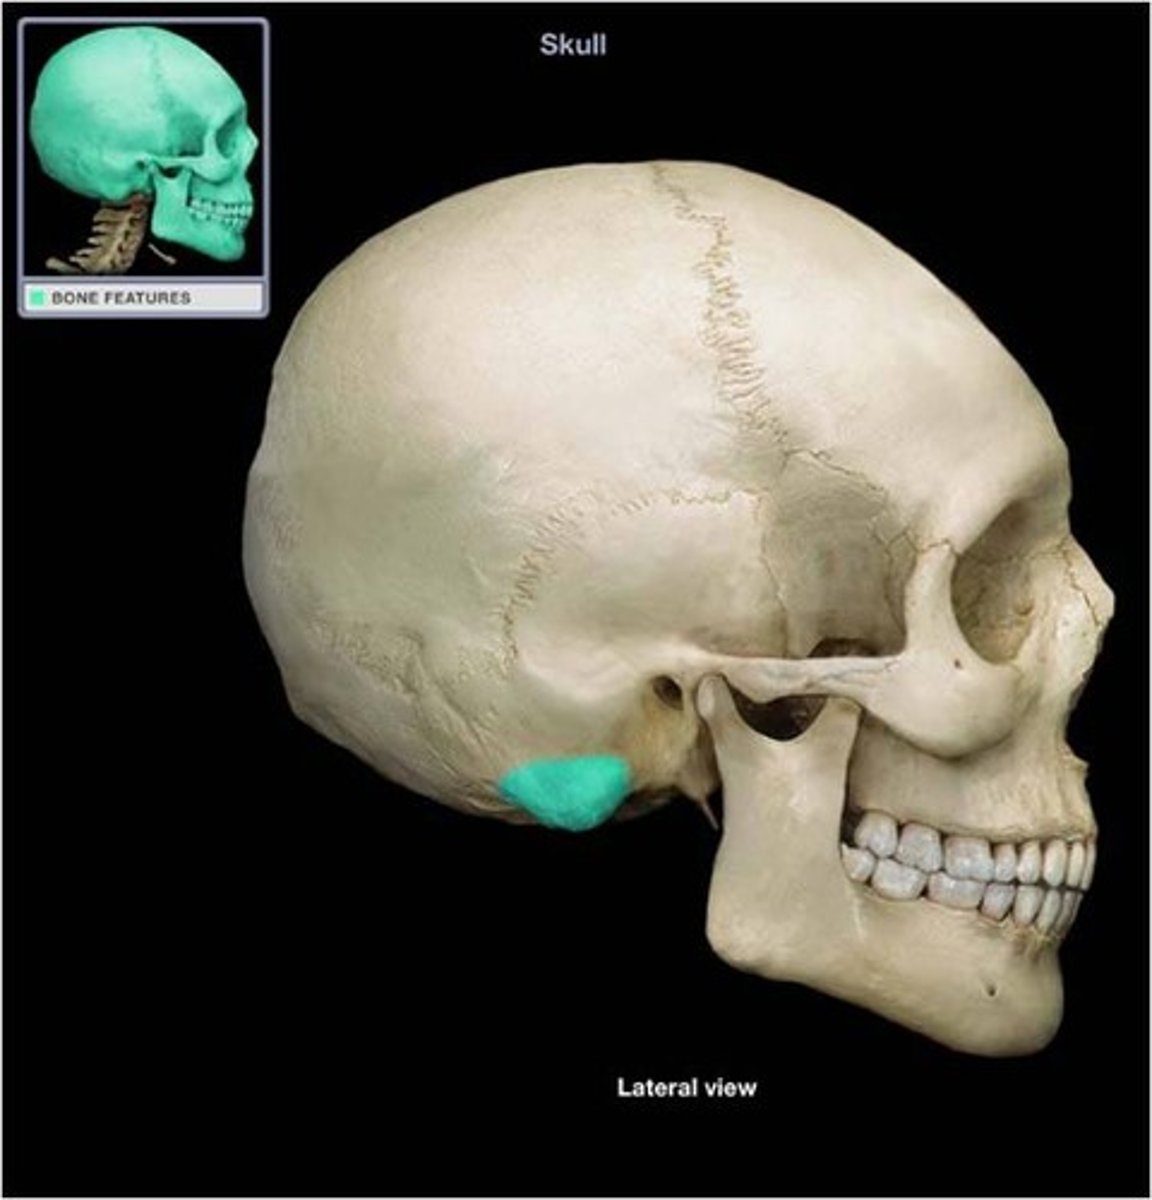

mastoid process